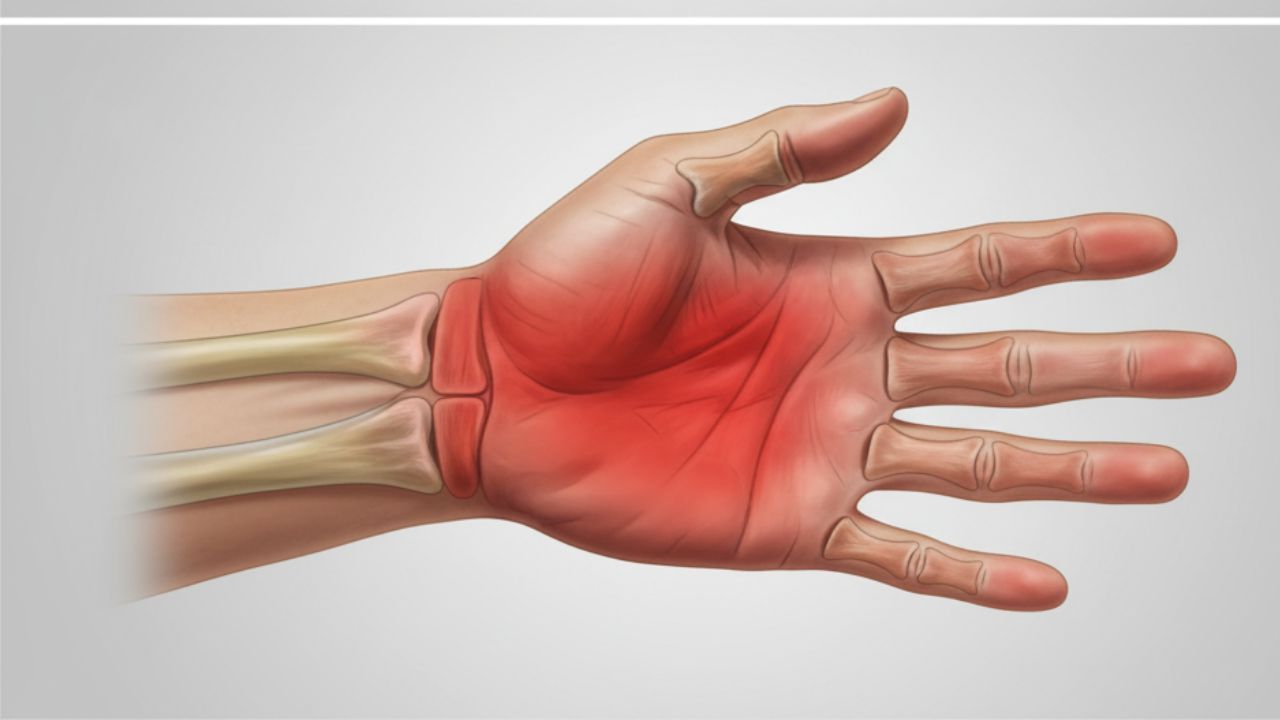

Síndrome do Túnel do Carpo Agendar consulta A Síndrome do Túnel do Carpo é uma condição comum que resulta da compressão do nervo mediano em